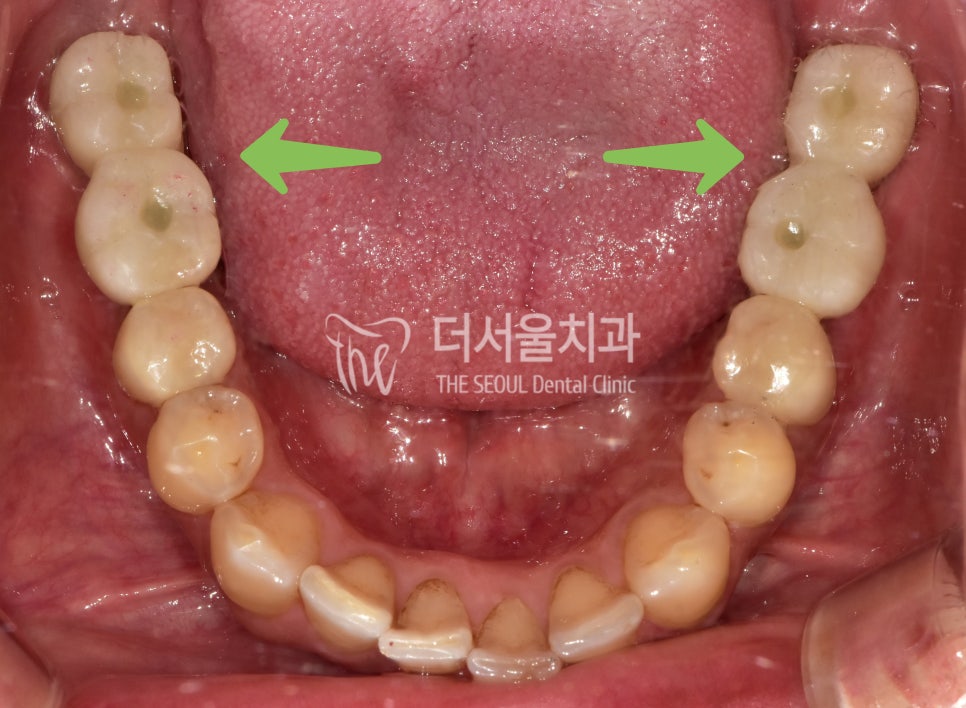

표시해 둔 곳이 치조골이

내려앉아 치아뿌리를 거의 잡아주지 못하고 있어

아래쪽 어금니가 흔들리고 있습니다.

사실상 양쪽 어금니가 둘 다 문제가 있어

구치부 기능을 못 하고 있는 것인데요.

실제로 적용된 모습을 보면,

튼튼한 어금니가 생겨

이제 편안한 식생활을 가능하게 해줍니다.

기능, 심미성 모두 신경 써서

제작해 드렸습니다.